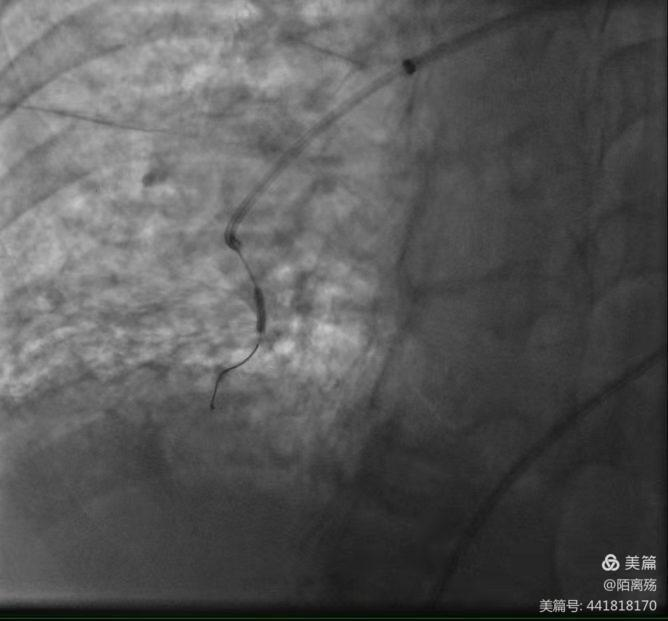

导丝沿着鞘管或引入导管送入肺动脉内,通过机化血栓狭窄病变至远端,接着沿导丝送入适合管腔大小的球囊。